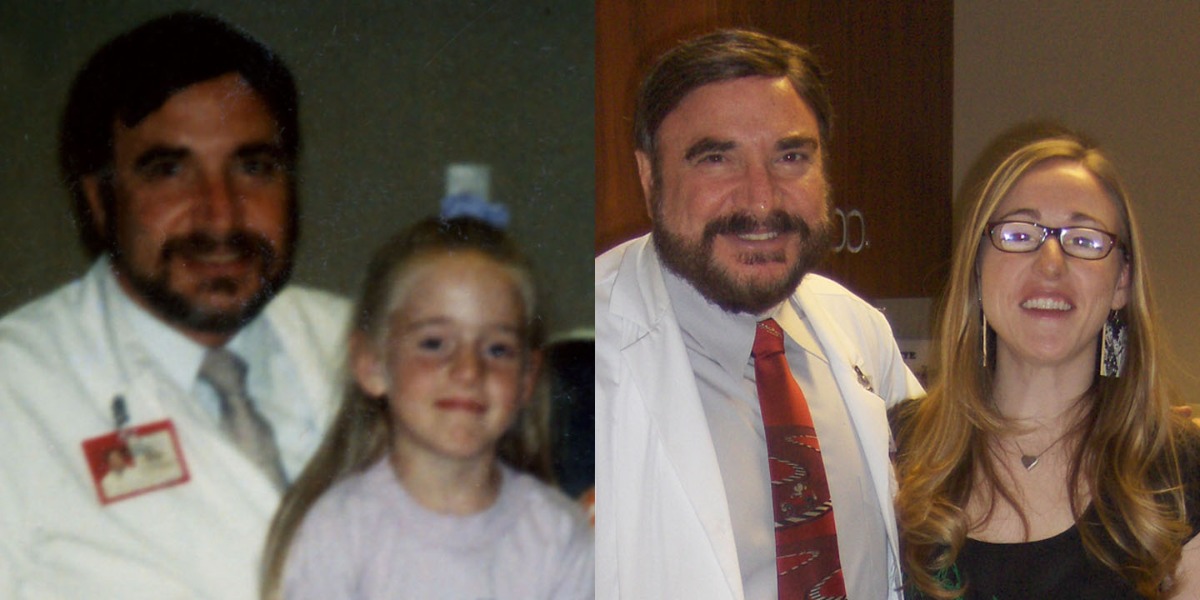

At birth, it was discovered I had congenital cataracts in both eyes, sharing the condition my brother had been born with 2 years prior. At only one week old, I underwent surgery to remove both clouded lenses. Despite some minimal complications during surgery, which still affect the vision in my right eye, my parents made sure I had the best possible care & opportunity to see. My case has been closely followed & written about in medical journals.

I have worn soft contacts, hard contacts & RGP contacts since surgery in 1983, which enabled me to have a normal & active life!

At birth, it was discovered I had congenital cataracts in both eyes, sharing the condition my brother had been born with 2 years prior. At only one week old, I underwent surgery to remove both clouded lenses. Despite some minimal complications during surgery, which still affect the vision in my right eye, my parents made sure I had the best possible care & opportunity to see. My case has been closely followed & written about in medical journals.

MegN FB ALBUMS I have worn soft contacts, hard contacts & RGP contacts since surgery in 1983, which enabled me to have a normal & active life!